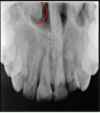

identify the anatomical structure below.

incisive (nasopalatine) foramen